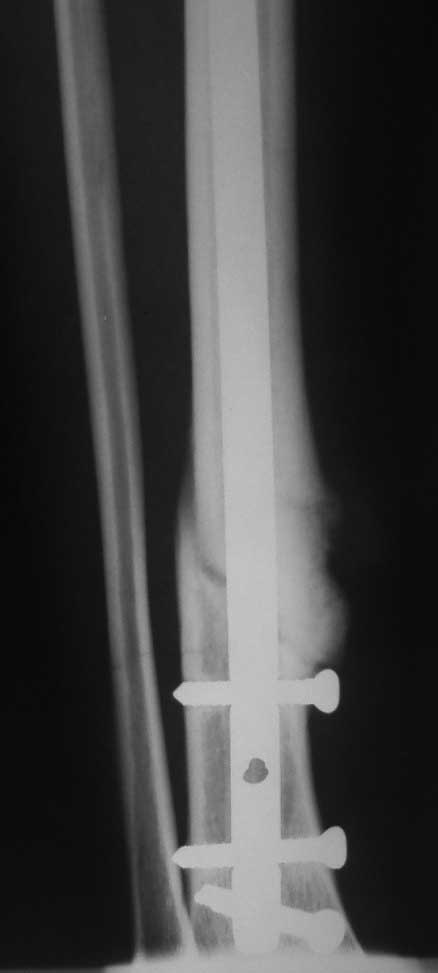

Очень интересная тема – дистальное блокирование при инфраистмальных переломах. К сожалению, аргументировано её осветить не представляется возможным в жёстких рамках поста. С моей точки зрения, неадекватное дистальное блокирование при инфраистмальных переломах большеберцовой кости является наиболее частой причиной неудач при интерлокинге. Можно ожидать проблем, если блокирование таких переломов выполняется только во фронтальной плоскости. Даже третий блокирующий винт, проведенный в сагиттальной плоскости, не всегда гарантирует необходимую стабильность (пример 1-1 – 1-3 во вложенном файле). Нестабильность фиксации случается, как правило, из-за того, что диаметр блокирующих винтов меньше диаметра блокирующих отверстий стержня, что позволяет блокирующим винтам (а значит и дистальному отломку) отклонятся от перпендикулярного положения относительно стержня. Чем больше разница в диаметрах, тем больше угол возможного отклонения. Несколько большую стабильность обеспечивают блокирующие винты, заворачивающиеся в стержень (отмечены стрелками). Мы для себя взяли за правило выполнять дистальное блокирование всех инфраистмальных переломов минимум тремя винтами, проведенными в разных плоскостях (пример 2-1 – 2-3 во вложенном файле). А с учётом того что мы не ограничиваем нагрузку в послеоперационном периоде и с целью уменьшения вероятности перелома блокирующих винтов при нагрузке - стандартная процедура дистального блокирования состоит во введении четырёх блокирующих винтов введенных в разных плоскостях (пример 3-1 – 3-2 во вложенном файле).

После применения такой методики не отмечено случаев несращения после интерлокинга инфраистмальных переломов.